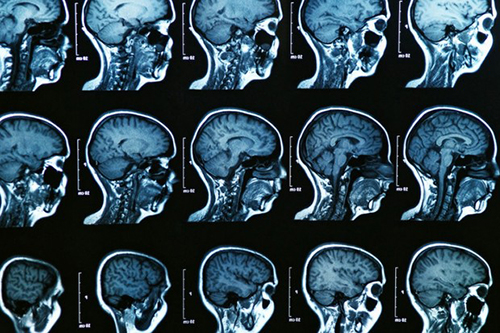

Университет Монреаля, сообщает SiFi, установил: аномально гиперактивные зоны мозга позволяют предсказать развитие болезни Альцгеймера. Данная гиперактивация наблюдается у людей без клинических симптомов болезни, еще до стандартно выявляемых когнитивных нарушений.

Известно, что данное заболевание может начать развиваться за 20-30 лет до появления симптомов. А максимально ранняя диагностика играет ключевую роль в сдерживании недуга. Ученые проверили метод на группе лиц с высоким риском развития болезни Альцгеймера, которые выполняли задание на память во время сканирования мозга с помощью фМРТ. Одна группа состояла из 28 человек, которые беспокоились о своей памяти, но не демонстрировали когнитивных нарушений при традиционных клинических тестах.

В другую группу вошли 26 человек с легкими когнитивными нарушениями. Исследователи обнаружили, что люди в первой группе имели аномально высокий уровень активации в нескольких ключевых областях мозга. Лица, уже имеющие легкие когнитивные нарушения, чаще демонстрировали снижение активности в этих областях.

По словам неврологов, активация определенных участков мозга на ранних стадиях болезни Альцгеймера может значительно усилиться, прежде чем потеря нейронов, вызванная заболеванием, приведет к явному снижению активации. В сочетании с другими показателями, такими как анализ крови и когнитивные тесты, этот тип анализа может помочь в более раннем обнаружении отклонений.